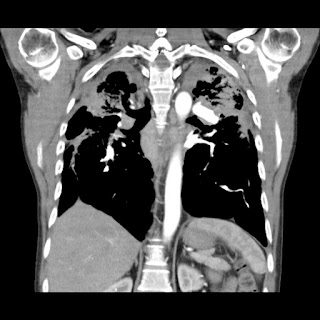

Hombre de 61 años asintomático. Colonoscopia demuestra válvula ileocecal ulcerada y estenótica. No hay antecedente de Enfermedad Inflamatoria Intestinal.

Con base en lo anterior el siguiente paso a seguir es?

a) Valoración por cirugía general.

b) Iniciar tratamiento con anti-inflamatorios e inmunosupresores.

c) Biopsia bajo guía ecográfica de las lesiones focales hepáticas.

d) Repetir colonoscopia.